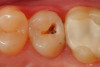

Fig 1. A preoperative occlusal view of tooth No. 13 that has a “stain” in the occlusal groove that does not “stick” with an explorer.

Figure 1

Fig 2. After a fissurotomy bur is used to conservatively open into the groove, a rather extensive carious area is discovered.

Figure 2